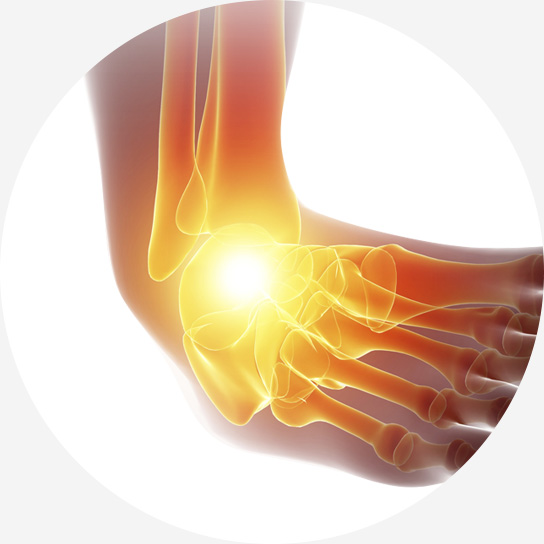

발목 인대는 발목 관절의 안정성을 유지하고, 발의 과도한 움직임을

제한하여 발목 관절을 보호하는 역할을 합니다.

걷거나 뛰는 등의 일상적인 활동을 가능하게 하고, 발목 관절의

정상적인 기능을 유지하는 데 필수적인 역할을 합니다.